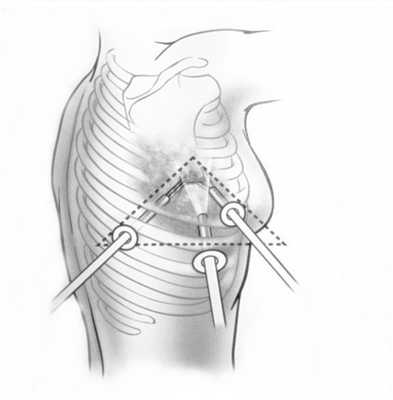

При невозможности получить образец ткани для исследования эндоскопически применяются инвазивные методы: трансторакальная биопсия, медиастиноскопия, видеоторакосокпия. Последние два метода — это серьезные операции, которые проводятся в специализированных медицинских учреждениях.

При обращении с любыми объемными образованиями в грудной стенке обязательно назначается комплекс уточняющих и дифференциально-диагностических исследований: рентгенография органов грудной клетки, КТ или МРТ, лабораторные анализы, биопсия.

В случаях безболезненного доброкачественного новообразования, как правило, пациентов больше беспокоит (или, наоборот, не беспокоит вообще) косметический дефект, иногда достигающий степени деформации грудной клетки. Однако в первую очередь следует принимать во внимание реальную вероятность малигнизации опухоли. Поэтому методом выбора является хирургическое удаление опухоли грудной стенки, независимо от ее гистологического характера.

Если подтверждена злокачественная природа опухоли, дальнейшая курация оказывается (в зависимости от ряда индивидуальных факторов и показателей) по стандартным протоколам комбинированного онкологического лечения, включающего хирургические, лучевые и химиотерапевтические методы. Одним из решающих факторов в статистике успешности играет своевременность выявления и начала лечения.